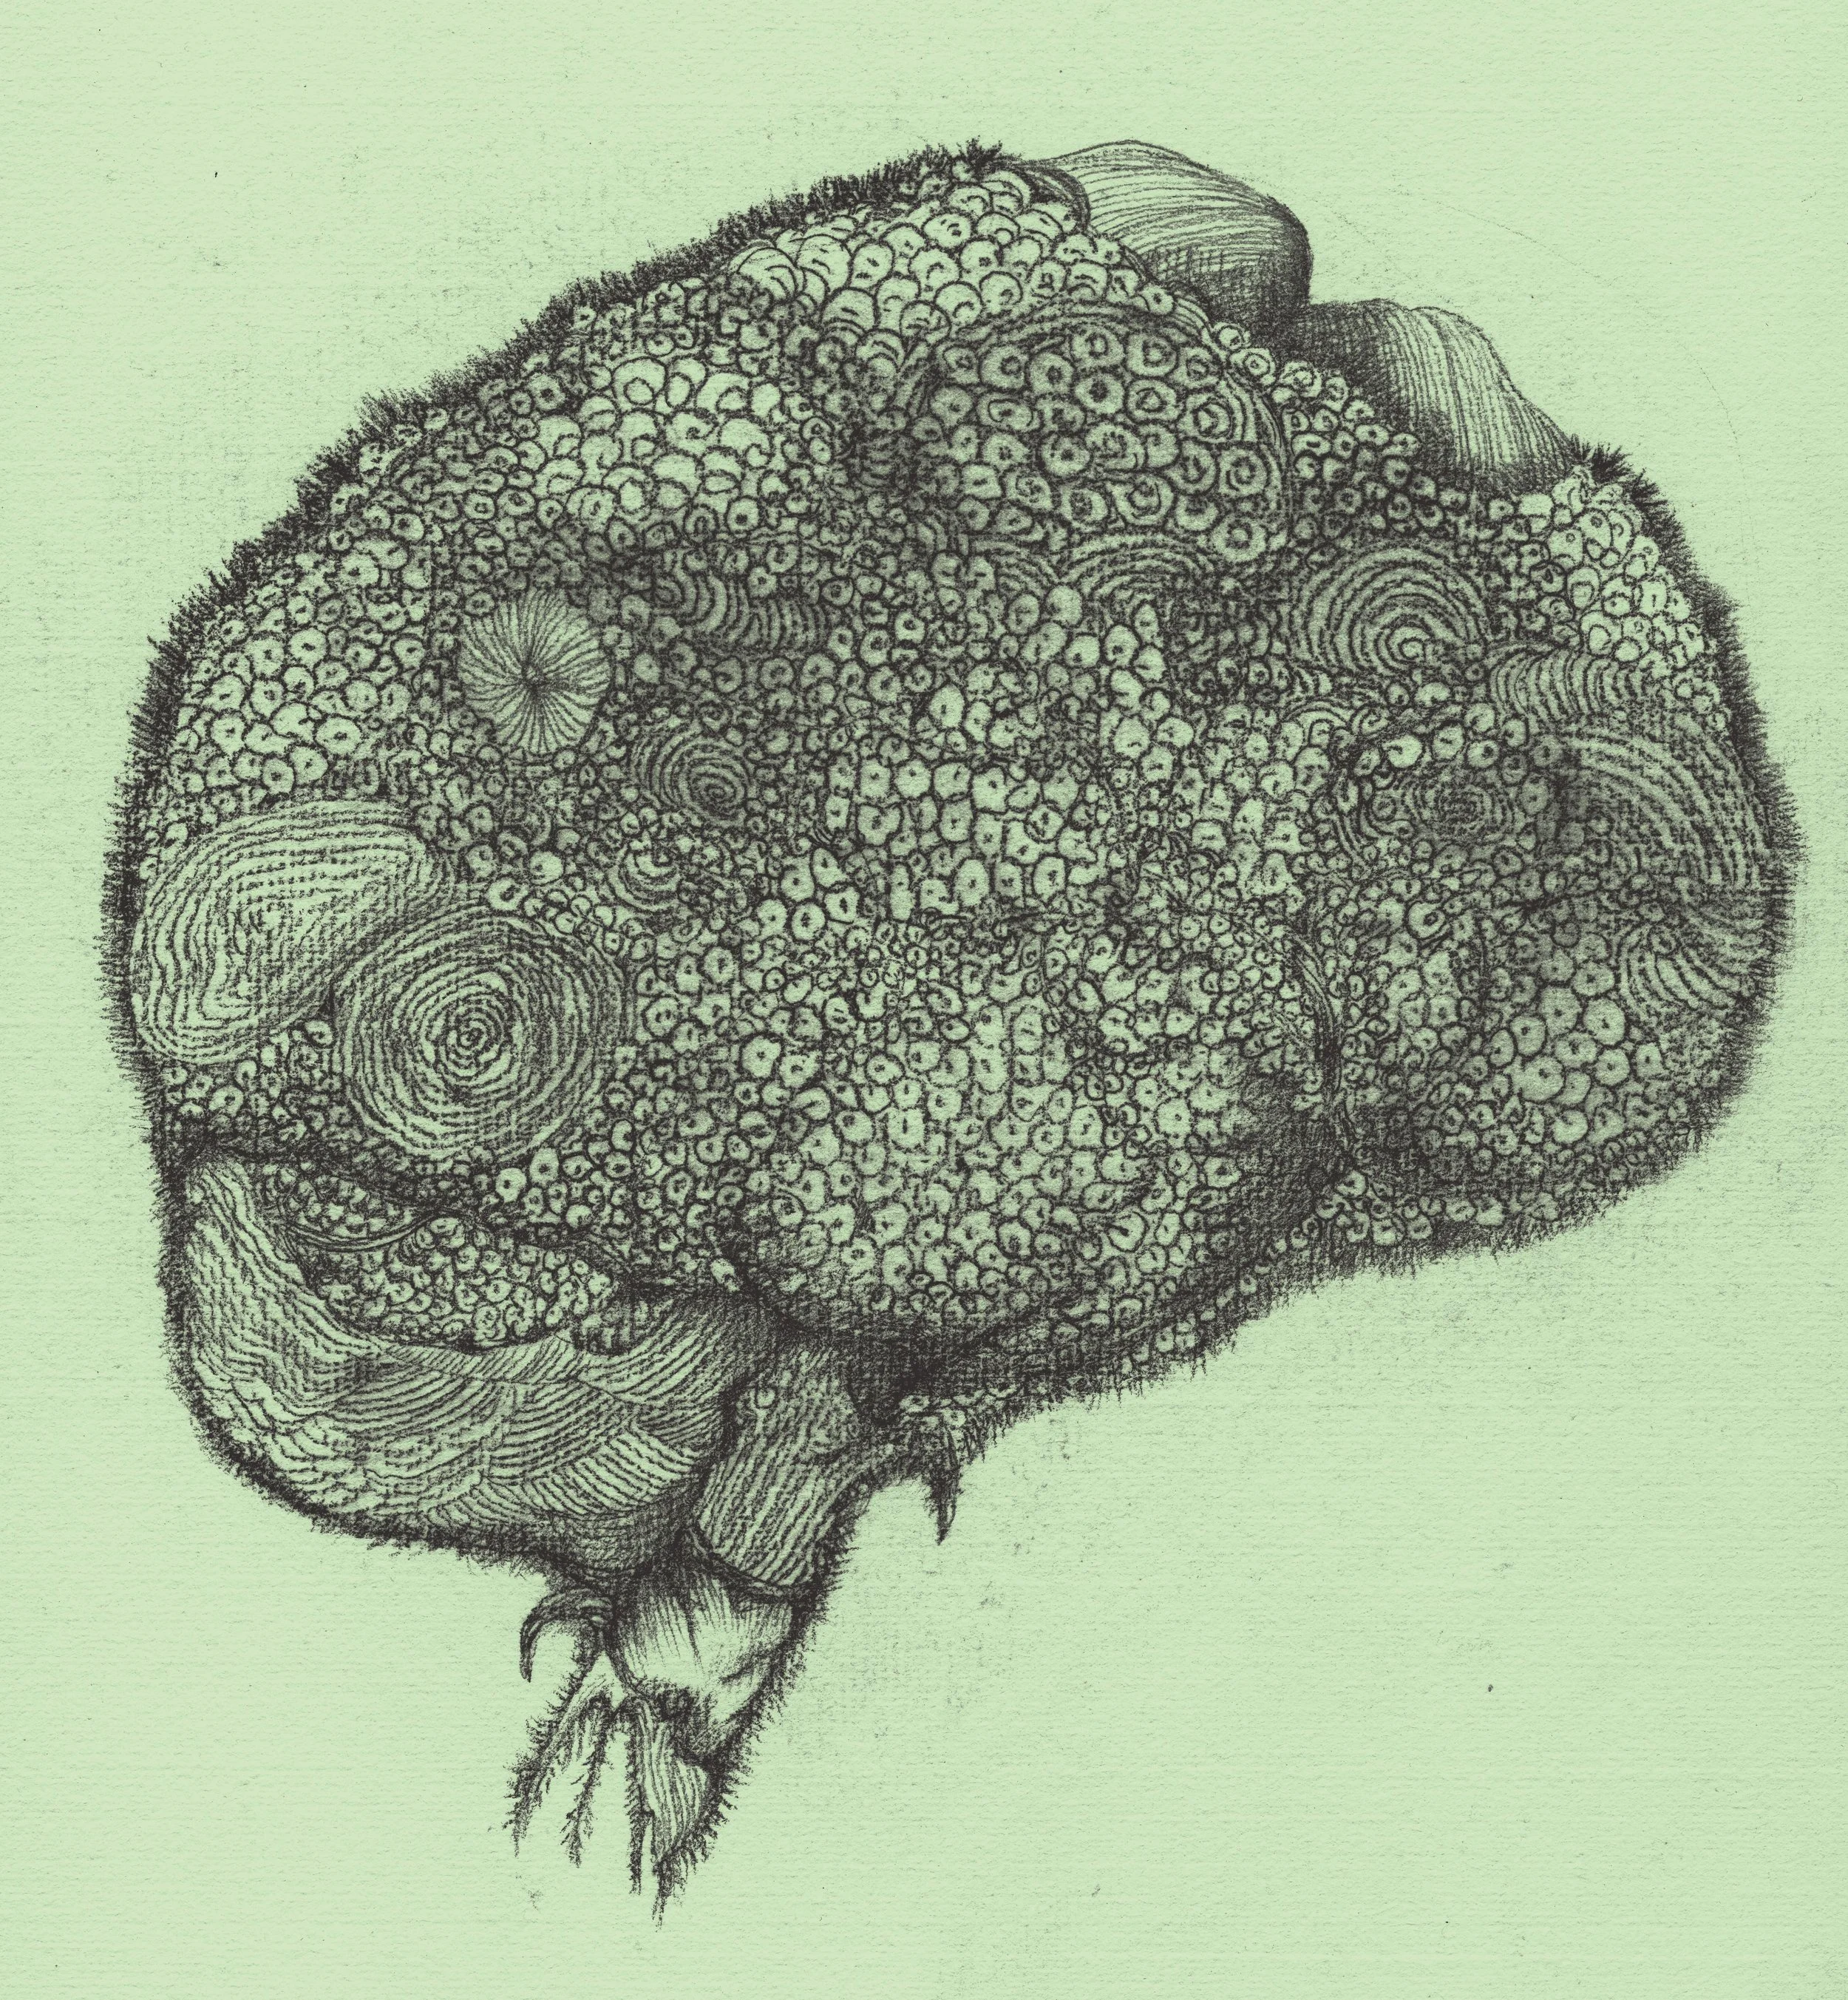

腦梗(Cerebral infarction)

Vegetative Brain (植腦)

Brain Fog 1 (腦霧)

Brain Fog 2(腦霧)

Brain Fog 3 (腦霧)

Brain Fog 4(腦霧)

Brain Fog 5 (腦霧)

Brain Fog 6(腦霧)

Brain Fog 7(腦霧)